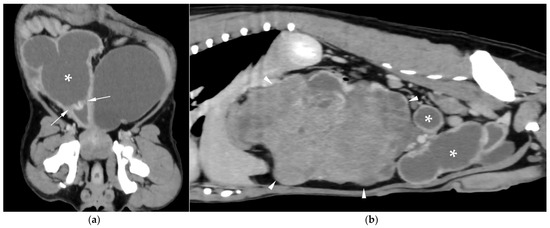

Computed Tomographic and Ultrasonographic Features in Three Dogs with Infected Uterus Masculinus and Concurrent Genital Neoplasia

Uterus masculinus is a rare disorder of sexual development in males, characterized by the presence of tubular female genitalia. Diagnostic imaging reports of infected uterus masculinus are limited. We describe the ultrasonographic and computed tomographic findings in three dogs, all presenting with abdominal distension, pain, and systemic infection. Imaging consistently revealed a fluid-filled, bicornuate structure arising from the prostate. In two dogs, the horns extended through the inguinal rings to the scrotal testes; in the third, with a prior left orchiectomy, both horns were intra-abdominal, the right ending in a peritoneal mass. Surgery and histopathology confirmed infected uterus masculinus, with Escherichia coli isolated from urine in all dogs and from the structure in two. Two dogs had Leydig cell tumors, one with concurrent uterine neoplasia; the third had an ovarian or ovotesticular granulosa cell tumor. Although rare, infected uterus masculinus is potentially life-threatening and should be considered in male dogs with abdominal pain, distension, or systemic infection. This is the first case series describing combined ultrasonographic and tomographic features of infected uterus masculinus, including novel findings such as cervix-like mural narrowing and fluid–fluid levels. It is also the first imaging description of an ovarian or ovotesticular tumor in a dog with uterus masculinus. Full article

Figure 1